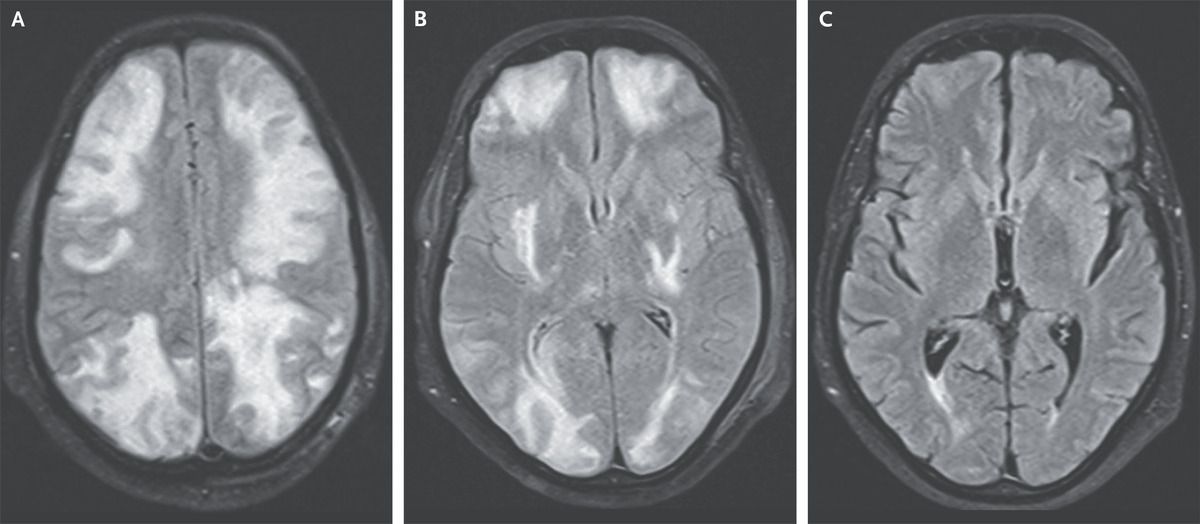

A 35-year-old man with IgA nephropathy presented to the emergency department with a 1-day history of confusion, blurry vision, and seizures. Two weeks before presentation, he had started receiving cyclosporine to treat the IgA nephropathy. His blood pressure was 160/80 mm Hg. Physical examination was notable for drowsiness and decreased visual acuity. A funduscopic examination was normal. T2-weighted magnetic resonance imaging (MRI) of the head with fluid-attenuated inversion recovery sequencing showed hyperintensities in the cortical and subcortical white matter in a holohemispheric watershed pattern — findings consistent with vasogenic edema (Panels A and B show findings at different axial levels). Findings on magnetic resonance angiography and venography were normal. A diagnosis of posterior reversible encephalopathy syndrome (PRES) due to cyclosporine use was made. Despite the name of the syndrome, PRES does not affect only the posterior parts of the brain. The condition may be associated with hypertension, kidney disease, or immunosuppressive therapy, as in this patient. One week after cyclosporine therapy was stopped, the patient’s symptoms and MRI findings had resolved (Panel C).